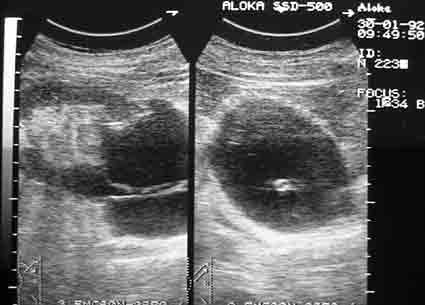

Архивные сонограммы, редкий случай.

На первый взгляд многокамерная киста.

Полостное образование с анэхогенным содержимым циркулярно охватывающее проксимальный отдел мочеточника, вызывающее уростаз. Предположу, что его можно назвать периуретеральная киста .

Почечная артерия проходит в почечной парапельвикальной кисте.

Пациент был оперирован, урологи были удивлены не меньше моего.

Жаль, что тогда не было ЦДК.